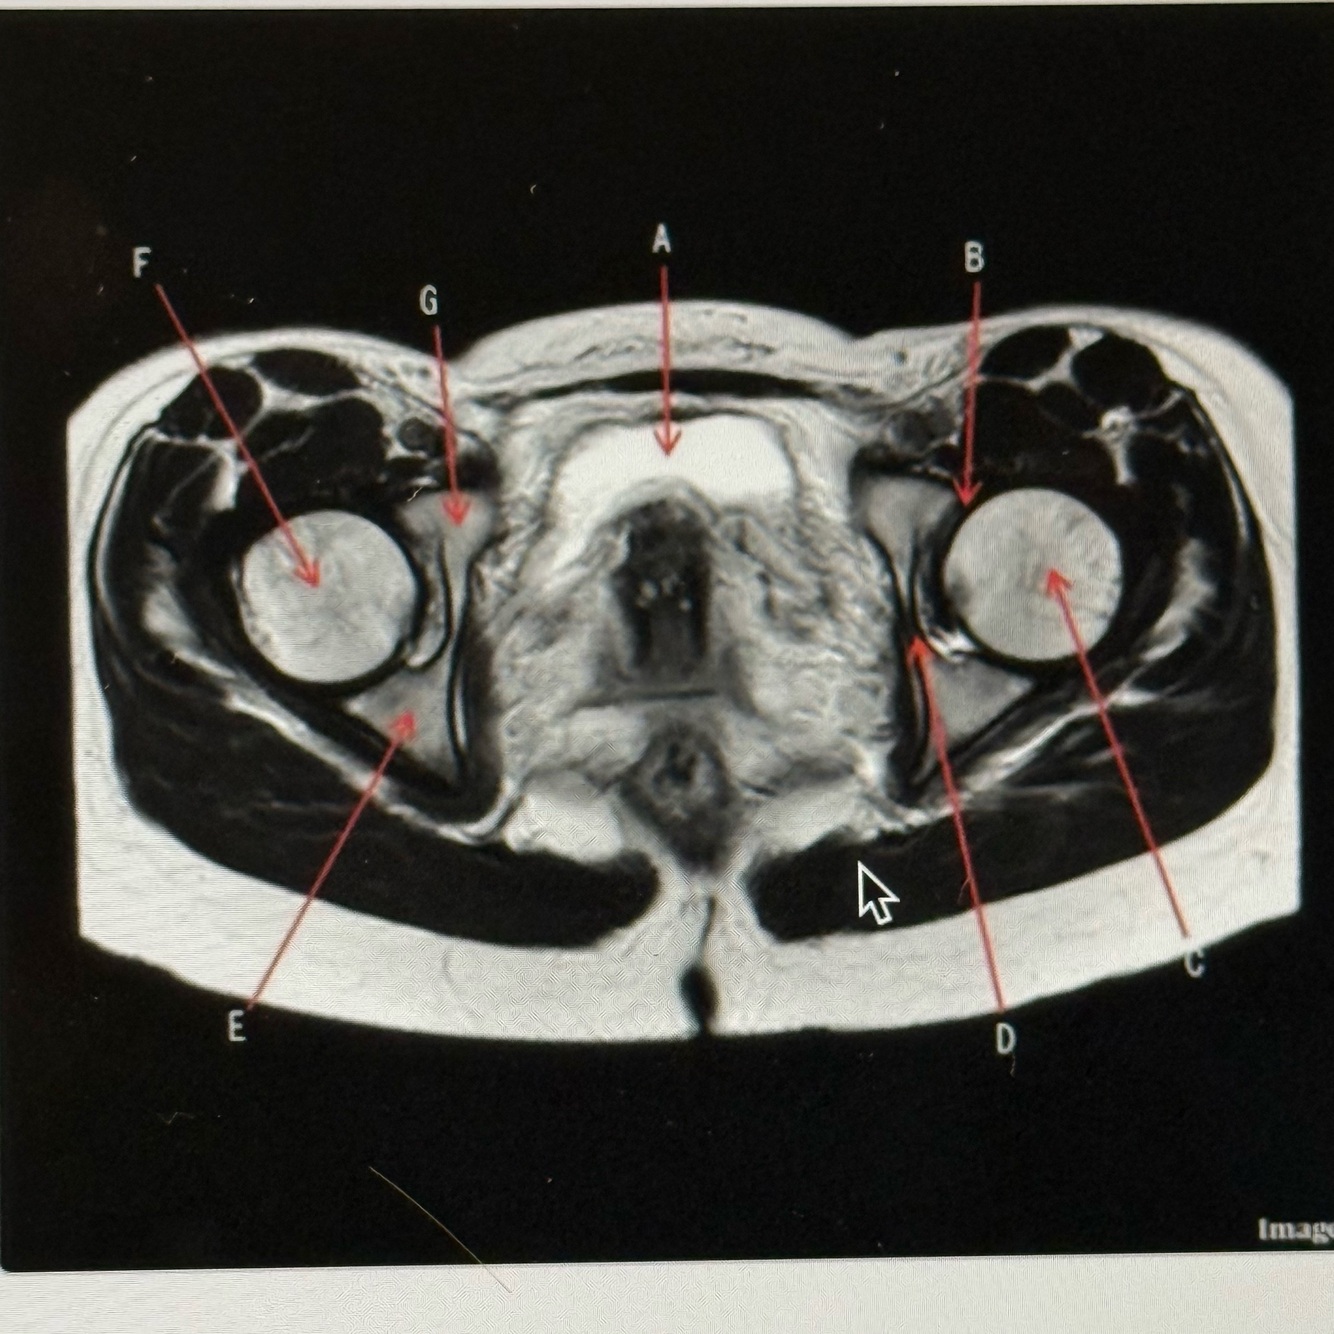

The image below is a ______ weighted image acquired in the _____ scan plane.

A

T2; Axial

5

Q

Letter A is pointing to the

Bladder

6

Letter B is pointing to the

Labrum

1

Letter D points to

Acetabulum

2

Letter E points to the

Ischium

3

Letter G points to the

Superior pubic ramus